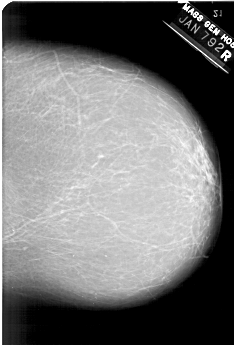

A_1380_1.RIGHT_CC

RIGHT_CC LINES 6196 PIXELS_PER_LINE 4201 BITS_PER_PIXEL 12 RESOLUTION 43.5 NON_OVERLAY